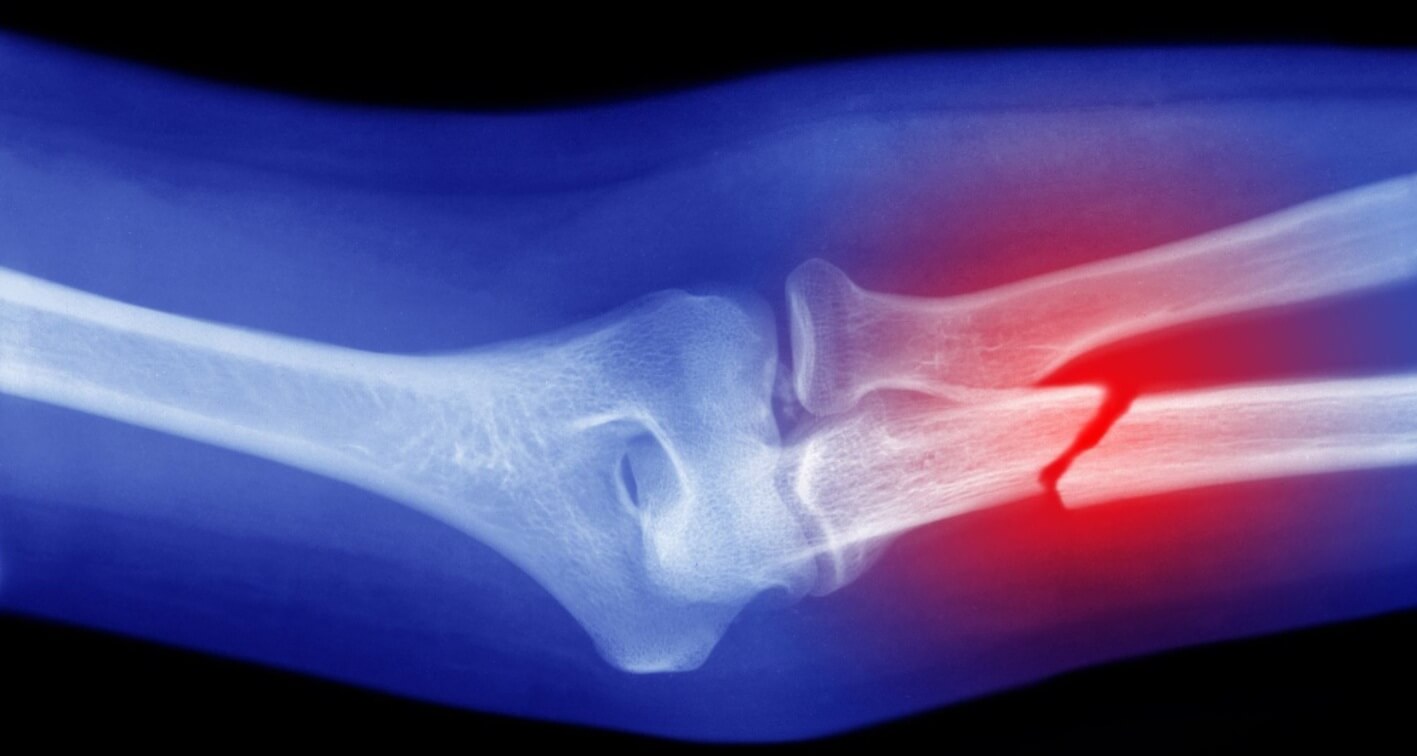

Importância do diagnóstico por imagem

O diagnóstico definitivo de uma fratura geralmente requer exames de imagem. As principais modalidades incluem:

- Radiografia: Método mais comum e acessível para visualizar fraturas.

- Tomografia computadorizada (TC): Oferece imagens detalhadas, especialmente útil em fraturas complexas.

- Ressonância magnética (RM): Pode detectar fraturas não visíveis em radiografias, especialmente em ossos pequenos.